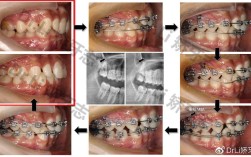

(图片来源网络,侵删)通过更换结扎丝(如不锈钢丝结扎、弹性结扎圈)改变托槽与弓丝的紧密度,增强摩擦力或允许牙齿滑动,例如滑动法关闭间隙时需结扎丝宽松,而需要精细控制时需紧密结扎。